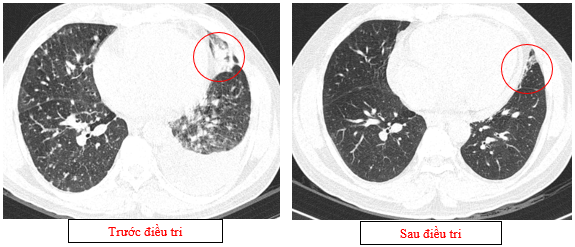

-         Chụp cắt lớp vi tính lồng ngực (08/2025): Khối rốn phổi trái ôm quanh nhánh phế quản thùy dưới trái kích thước 28x26mm, dày tổn chức kẽ vách liên tiểu thùy và nhiều nốt đặc lan tỏa khắp nhu mô, đường kính <7mm. Màng phổi trái có vài nốt đặc ngấm thuốc nốt lớn nhất kích thước 17x15mm  Khoang màng phổi trái có dịch dày 54mm. Nhiều hạch to trung thất, rốn phổi hai bên và hố thượng đòn có hoại tử trung tâm, hạch lớn nhất kích thước trục ngắn 22mm.

Hình 01: Nhiều hạch to trung thất, rốn phổi hai bên và hố thượng đòn có hoại tử trung tâm, hạch lớn nhất kích thước trục ngắn 22mm

Hình 02: Khối rốn phổi trái ôm quanh nhánh phế quản thùy dưới trái kích thước 28x26mm, dày tổn chức kẽ vách liên tiểu thùy và nhiều nốt đặc lan tỏa khắp nhu mô, đường kính <7mm.

Hình 03: Màng phổi trái có vài nốt đặc ngấm thuốc nốt lớn nhất kích thước 17x15mmKhoang màng phổi trái có dịch dày 54mm

-         Chụp cắt lớp vi tính lồng ngực (11/2025): Màng phổi vùng rốn phổi trái dày,dày tổ chức kẽ vùng ngoại vi đáy phổi hai bên. Màng phổi trái có vài nốt đặc ngấm thuốc nốt lớn nhất kích thước 17x15mm. Khoang màng phổi hai bên không có dịch – khí (Tổn thương giảm đáng kể so với phim chụp 08/2025). Trung thất, rốn phổi hai bên, hố thượng đòn trái có vài hạch, hạch lớn nhất kích thước 12x6mm. Vài nốt đặc xương rải rác thân đốt sống, các cung xương sườn hai bên.

Hình 07: Hạch thượng đòn trái giảm đáng kể kích thước, từ 22mm còn 7mm sau điều trị.

Hình 08: Khối u đáp ứng gần hoàn toàn, chỉ còn tổn thương dạng kính mờ, các tổn thương dày tổ chức kẽ vách liên tiểu thuỳ, nốt đặc rải rác 2 trường phổi cũng gần như biến mất.

Hình 09: Không còn tổn thương tràn dịch màng phổi trái trên phim chụp